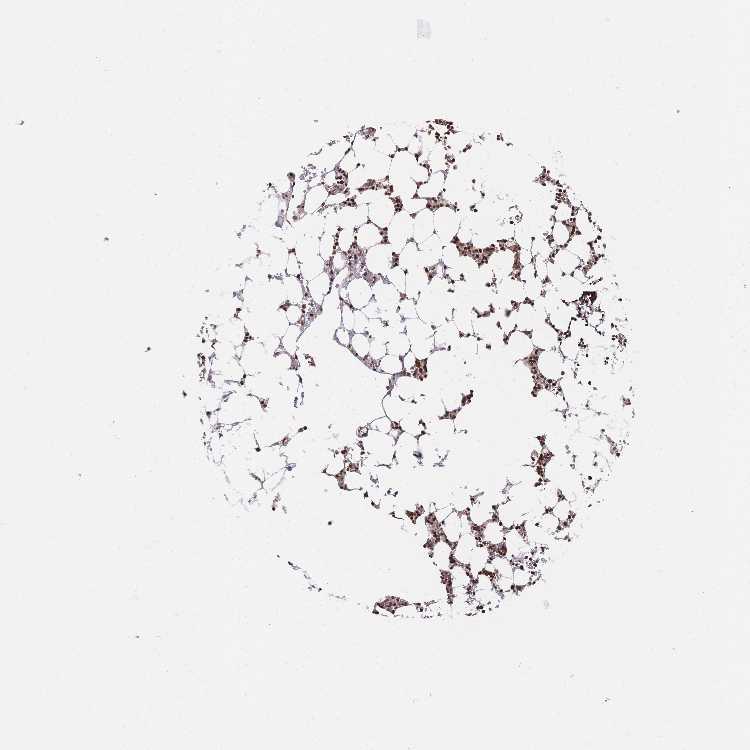

TISSUE PRIMARY DATA BONE MARROW Show tissue menu

BONE MARROW - Antibody stainingi

Antibody staining in the annotated cell types in the current human tissue is reported as not detected, low, medium, or high, based on conventional immunohistochemistry profiling in selected tissues. This score is based on the combination of the staining intensity and fraction of stained cells.

Each image is clickable and will lead to virtual microscopy that enables deeper exploration of all samples and also displays staining intensity scores, fraction scores and subcellular localization as well as patient and tissue information for each sample.

Antibody HPA048728Antibody HPA053422Antibody CAB026035

Hematopoietic cells HighHighHigh